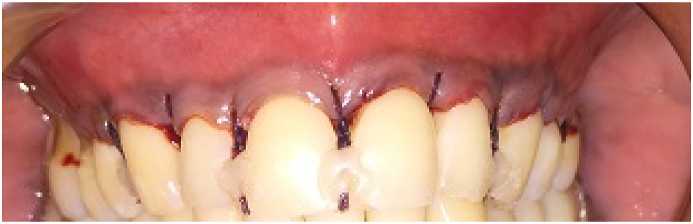

2.8. M-CAF (control group)

Coronally advanced flap as modified by Zucchelli and De Sanctis was performed.4 An envelope flap was designed by placing oblique submarginal incisions at the interdental areas and intrasulcular incisions were placed using a15C blade (Fig. 2a, Fig. 2ba and b). The oblique incisions started at the cementoenamel junction of the central tooth involved. The flap was elevated with a split-full-split approach in the corono-apical direction. Split thickness flap was elevated in the most apical part of the flap to provide tension free coronal advancement (Fig. 2c). The interdental papillae were de-epithelialized and the modified coronally advanced flap was positioned coronally to the CEJ and secured using resorbable vicryl sling sutures. To immobilize the gingival margin which is critical during healing phase composite bonded coronally anchored sutures were placed for 3 weeks for better stability of the flap coronally (Fig. 2 d).

Coronally advanced flap covering the recession defects and stabilised using sling and coronally anchored bonded sutures.